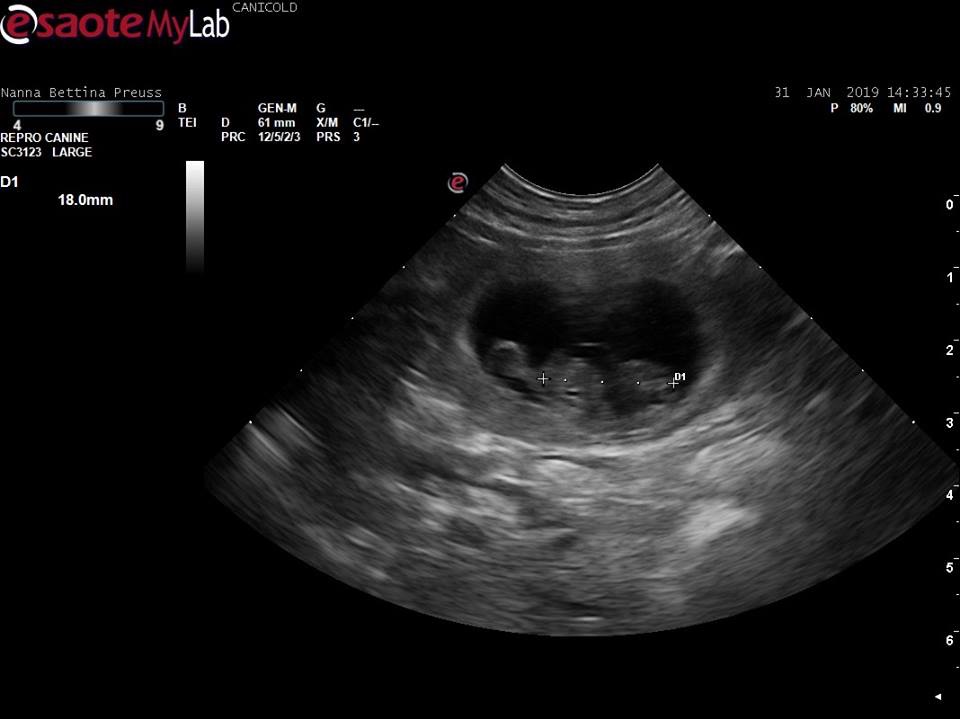

• Nanna

Hvalpe 🐾🐾🐾